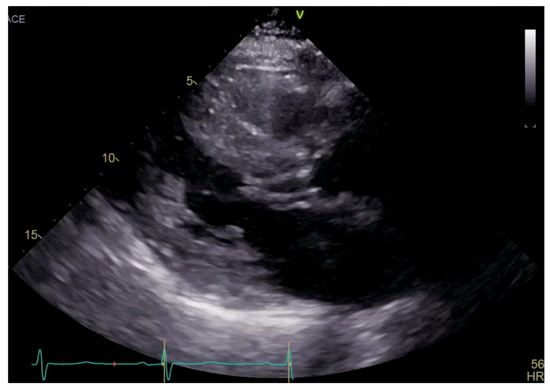

Figure 1.

Parasternal long axis view on TTE showing left ventricular hypertrophy and SAM.

Transthoracic echocardiogram (TTE) showed severe asymmetric left ventricular hypertrophy, preserved left ventricular ejection fraction at 65–70%, systolic anterior motion (SAM) of the mitral valve (Figure 1 and Supplementary Video S1), left ventricular outflow tract (LVOT) obstruction with a peak velocity of 7.1 m/s at rest and an eccentric, posteriorly directed mitral regurgitant jet (Figure 2). Pharmacological myocardial perfusion SPECT with gated imaging was obtained one year prior to presentation and showed normal myocardial perfusion, left ventricular volume and systolic function. Cardiac magnetic resonance imaging showed left ventricular hypertrophy with a maximal thickness of 1.7 cm at the mid-ventricular septum and late gadolinium enhancement in the lateral and inferior half of the left ventricle, the basal inferolateral wall, the apical lateral walls and the apical anterior wall (Figure 3a,b). These findings were consistent with a diagnosis of HCM with outflow tract obstruction; thus, the patient was started on beta blockers.